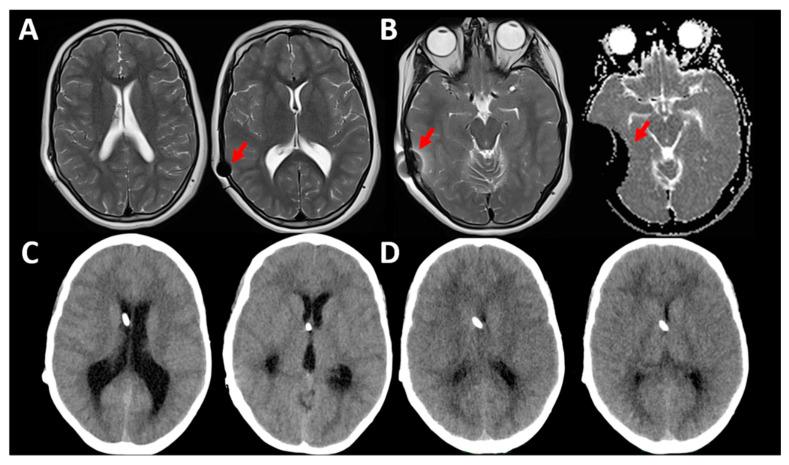

如何为正常压力脑积水患者选择分流器:选择最佳分流装置的简短指南

How to Choose a Shunt for Patients with Normal Pressure Hydrocephalus: A Short Guide to Selecting the Best Shunt Assembly.

Most patients with hydrocephalus are still managed with the implantation of a cerebrospinal fluid (CSF) shunt in which the CSF flow is regulated by a differential-pressure valve (DPV). Our aim in this review is to discuss some basic concepts in fluid mechanics that are frequently ignored but that should be understood by neurosurgeons to enable them to choose the most adequate shunt for each patient. We will present data, some of which is not provided by manufacturers, which may help neurosurgeons in selecting the most appropriate shunt. To do so, we focused on the management of patients with idiopathic "normal-pressure hydrocephalus" (iNPH), as one of the most challenging scenarios, in which the combination of optimal technology, patient characteristics, and knowledge of fluid mechanics can significantly modify the surgical results. For a better understanding of the available hardware and its evolution over time, we will have a second look at the design of the first DPV and the reasons why additional devices were incorporated to control for shunt overdrainage and its related complications. We try to persuade the reader that a clear understanding of the physical concepts of the CSF and shunt dynamics is key to understand the pathophysiology of iNPH and to improve its treatment.

摘要

大多数脑积水患者仍通过植入脑脊液(CSF)分流器来治疗,其中脑脊液流动由压差阀(DPV)调节。本综述的目的是讨论一些流体力学的基本概念,这些概念经常被忽视,但神经外科医生应该理解,以便为每位患者选择最合适的分流器。我们将展示一些制造商未提供的数据,这些数据可能有助于神经外科医生选择最合适的分流器。为此,我们重点关注特发性“正常压力脑积水”(iNPH)患者的管理,这是最具挑战性的情况之一,在这种情况下,最佳技术、患者特征和流体力学知识的结合可以显著改善手术效果。为了更好地理解现有的硬件及其随时间的演变,我们将再次审视第一个压差阀的设计,以及为何要加入其他装置来控制分流器过度引流及其相关并发症。我们试图说服读者,清楚理解脑脊液和分流动力学的物理概念是理解iNPH病理生理学并改善其治疗的关键。